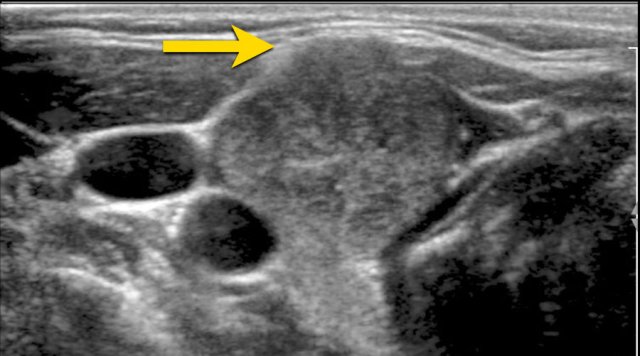

Mixed cystic/solid

In mixed cystic/solid lesions the amount of cystic and solid parts is not important.

This lesion gets 1 point for the mixed cystic/solid composition.